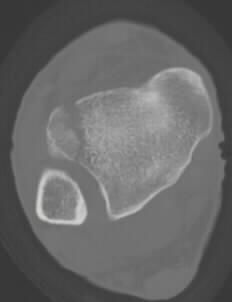

Hill-Sachs骨折

Hill-Sachs骨折指肱骨头压缩性骨折,当肩关节前脱位时,关节盂前缘撞击导致肱骨头后外侧压缩骨折。